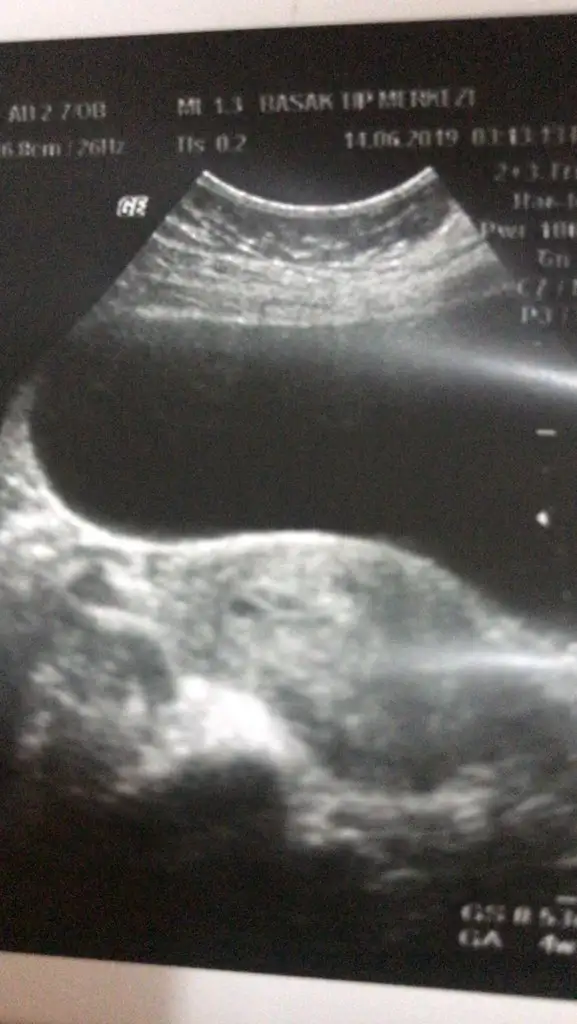

Ne kadar güzel sat tarihlerimiz yakın ..merak ettim kalp atışlarını duydunuz mu bi de sizin hcg en son kaç çıktı